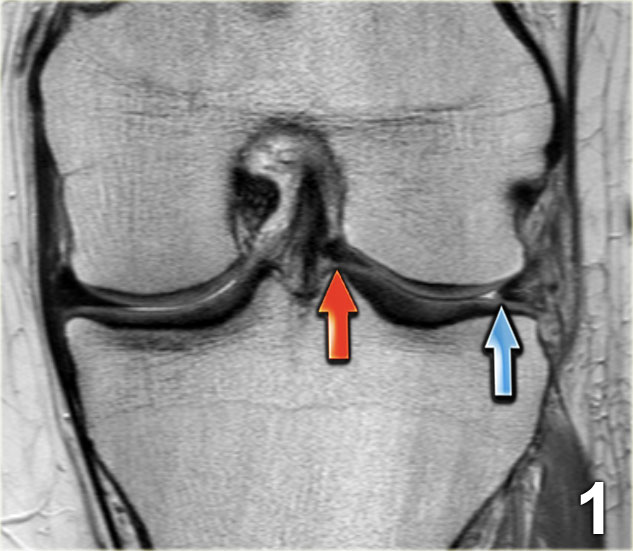

Chúng ta bắt đầu với lát cắt ở giữa của khảo sát.

Lưu ý thân sụn chêm bên có kích thước nhỏ với hình dạng bất thường (mũi tên xanh).

Phần bờ trong bị khuyết được nhìn thấy ngay phía ngoài dây chằng chéo trước (mũi tên đỏ). - Phần sụn chêm bị rách di lệch vào trong, tức là phần quai xách, có thể được theo dõi theo hướng ra sau trong hố gian lồi cầu.

Rách kiểu quai xách là loại rách dọc theo chiều đứng có kèm di lệch.

Mảnh bờ trong bị di lệch có hình dạng giống như quai của một chiếc xô.

Phần ngoại vi còn lại của sụn chêm, phần lớn hơn, có hình dạng giống như thân chiếc xô.

Loại rách này chiếm khoảng 10% trong tổng số các trường hợp rách sụn chêm.

Dấu hiệu PCL đôi

Dấu hiệu dây chằng chéo sau (PCL) đôi là một dải giảm tín hiệu nằm song song và ở phía trước-dưới so với PCL trên ảnh MRI mặt phẳng đứng dọc.

Đây là dấu hiệu có độ đặc hiệu cao trong chẩn đoán rách sụn chêm kiểu quai xô (3).